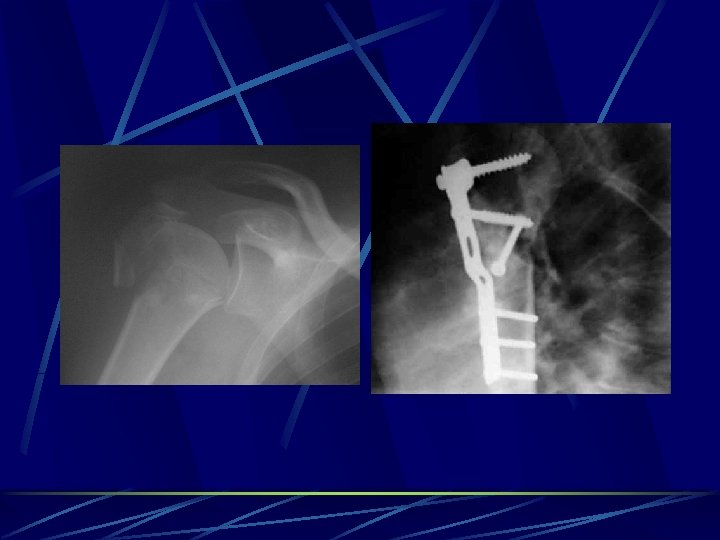

Plates and screws designs vary depending on the anatomic region and size of the bone used in the management of articular fractures allows early ROM and the use of muscles and joints strength and stability, neutralize forces Buttress plates counteract compression and shear - metaphysis and epiphysis used around joints to support intra-articular fractures Compression plates (DCP – Dinamic commpression plate, LC-DCP low contact dinamic commpression plate) counteract bending, shear, and torsion, eccentrically loaded holes in the plate used in long bones (fibula, radius, and ulna) Neutralization plates combination with interfragmentary screw fixation interfragmentary compression screws provide compression, plate neutralizes torsional, bending, and shear forces ( lag screws increases the stability of the construct) (fibula, radius and ulna, and humerus) Bridge plates - management of multifragmented diaphyseal and metaphyseal fractures.

Spetial types of osteosynthesis LISS ( less invasive stabilisation system) implants for MIPPO (minimal invasive percutane plate osteosynthesis) -Herbert´s screw – scafoid # DHS – NOF# basicervical PFN – NOF # pertrochanteric Phillos –prox. humerus DCS (dinamic condylar screw) and DFN (distal femoral nail) - dist. femur Pilon plate – dist. tibia